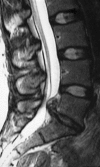

Low back pain